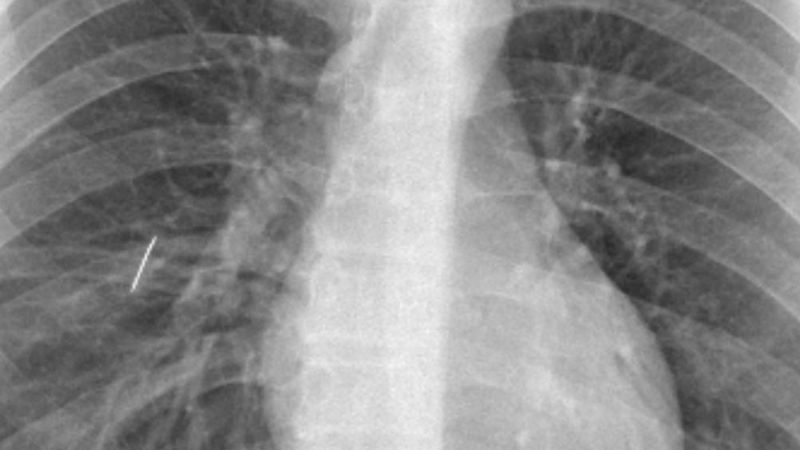

La operación, que se extendió durante aproximadamente una hora y media, estuvo a cargo del cirujano Fernando Lestussi junto al equipo del Servicio de Cirugía General. Por la complejidad y la ubicación del cuerpo extraño, se optó por una técnica quirúrgica más invasiva, aunque el paciente respondió favorablemente y no presentó complicaciones.

Un aspecto clave del procedimiento fue la intervención del equipo de Anestesiología, que realizó una intubación selectiva mediante fibrobroncoscopio. Esta técnica permitió ventilar un solo pulmón mientras el otro permanecía inactivo, facilitando así la extracción del objeto con mayor precisión y seguridad.

“El caso no podía derivarse por el alto riesgo que implicaba el traslado, por lo que debía resolverse en nuestro hospital. Es una gran satisfacción haberlo logrado con profesionales locales”, explicó el Dr. Lestussi, quien además destacó la importancia del trabajo conjunto entre los distintos servicios.